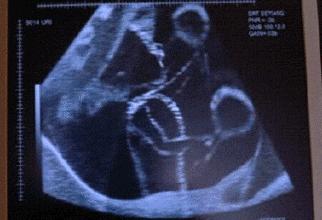

【孕7月:“看”到胎动】

怀孕7个月,羊水量比较大了,胎宝游起来就更舒心了,会多了很多踢腿的动作,而一些皮肤薄的孕妈,甚至直接能看到胎动,看着自己的肚子变形还真…蜜汁感觉。

这时候孕妈可以仔细感受下,胎动多是靠近胃部,向两侧扩大的。